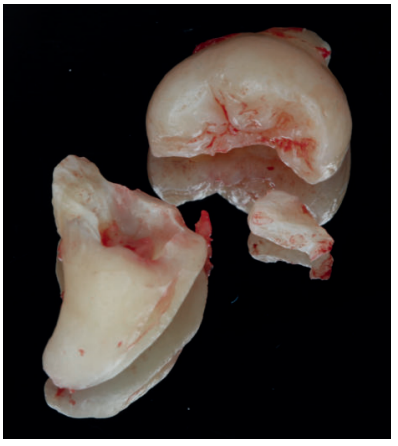

Los fragmentos coronal y radicular se limpiaron de restos de tejidos blandos, y secos, se introdujeron en la máquina Smart Dentin Grinder® (Kometa Bio, BIONER, España). Tras un ciclo de triturado de 3 segundos, y otro de tamizado de 20 segundos, el material obtenido (Figura 3) se limpió con la primera solución durante 12 minutos, y después durante 3 minutos con la segunda solución, para después transportar el material de injerto al alveolo, con presión controlada (Figura 4). Una vez compactado, se colocó una esponja de fibrina (Gelatamp® ) (Figura 5) y se suturó la herida con seda de 4/0, mediante dos puntos simples en la cara distal del segundo molar inferior izquierdo, un punto en cruz en la descarga y un punto en la papila (Figura 6). Se realizó una radiografía periapical intraoperatoria (Figura 7).